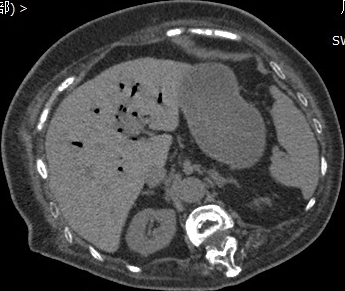

我们赶紧给患者安排了急诊腹部CT,从图片看肝内胆管存在多发积气,胆囊结石的位置与十二指肠关系密切,怀疑结石压穿了胆囊和十二指肠壁形成了内瘘。

急诊CT发现肝内胆管积气